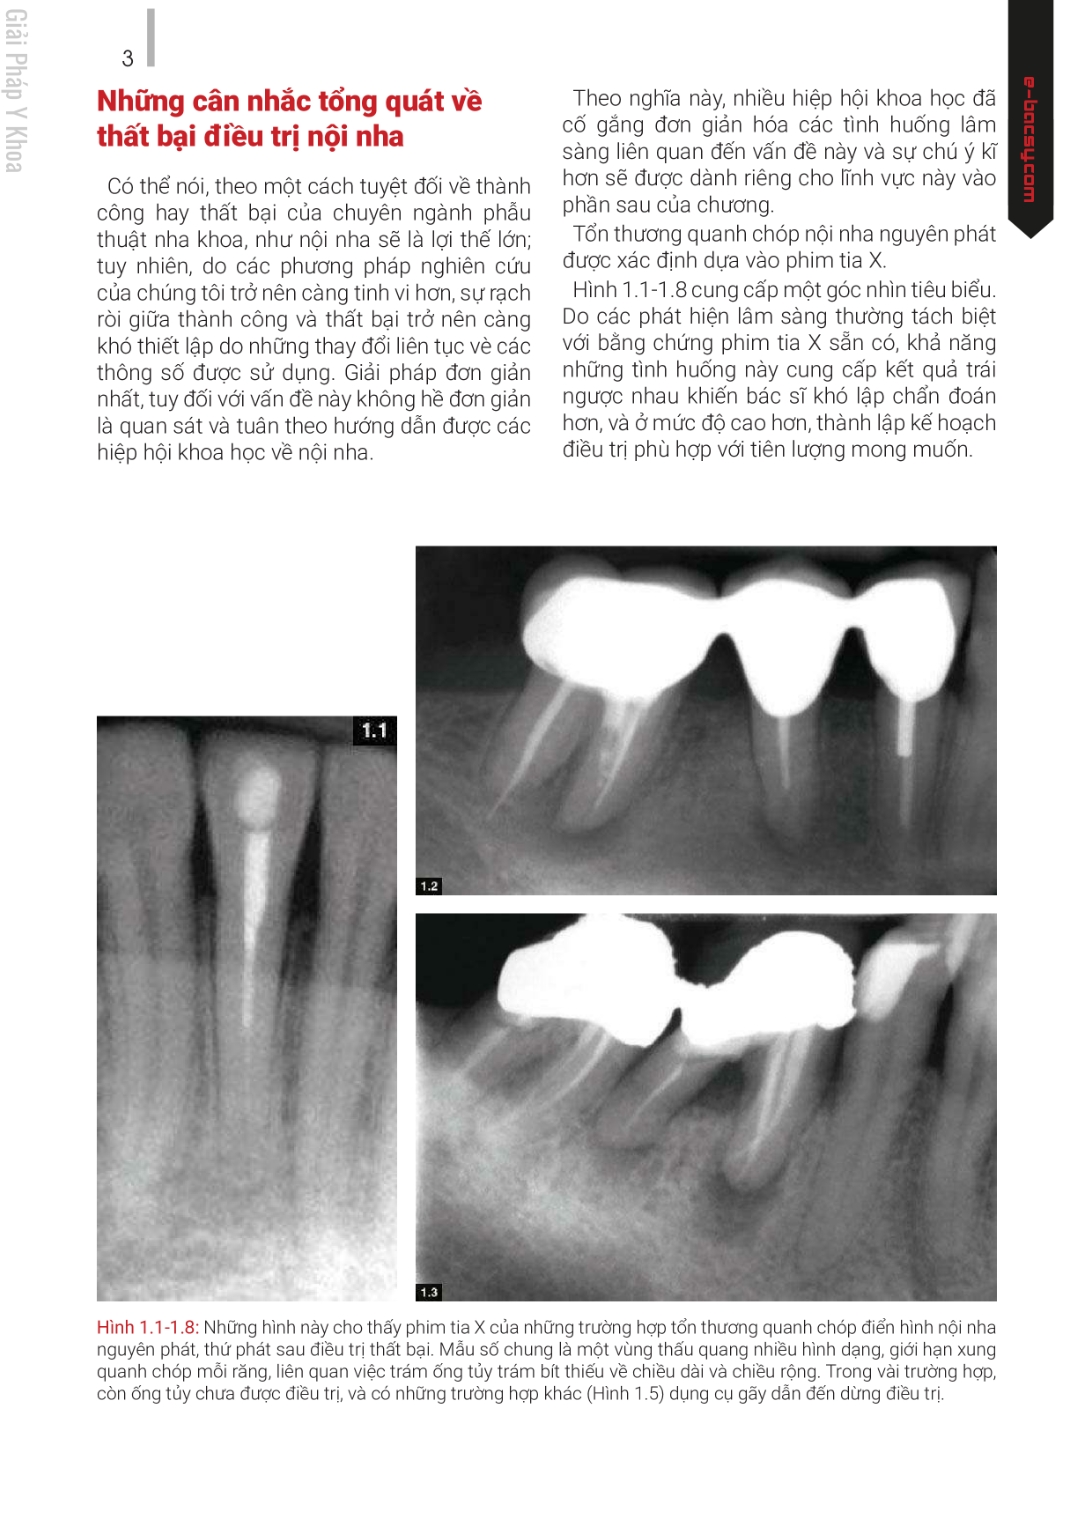

ĐIỀU TRỊ LẠI – NHỮNG GIẢI PHÁP SANG THƯƠNG QUANH CHÓP NGUỒN GỐC TỪ NỘI NHA